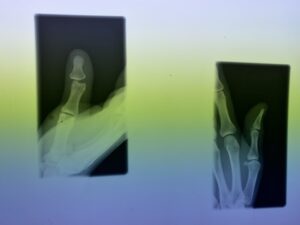

さわやか千葉県民プラザ(指骨骨折)